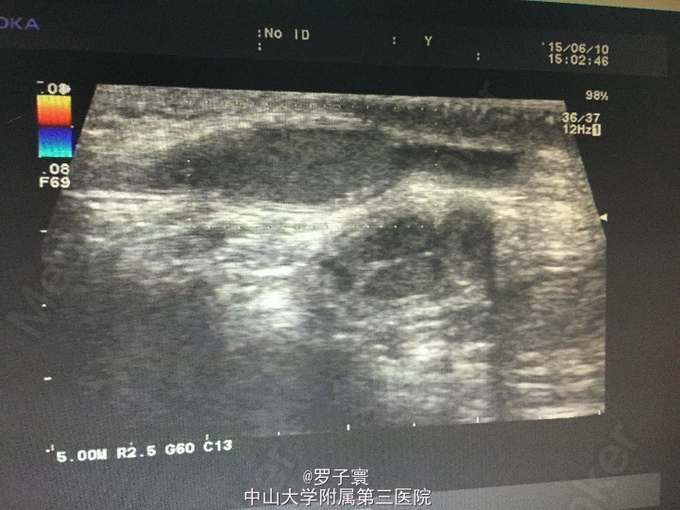

查体:阴茎呈男童外观,包茎,左侧阴囊空虚,未触及任何内容物,左侧腹股沟可触及睾丸样团块,质地软,大小1.4*0.6cm,无触痛,无粘连,站立活动后右侧阴囊可触及质软肿物,透过试验阳性,可扪及右侧睾丸,大小约1.5*0.8cm,触诊质地软,表面光滑,无硬结,无压痛,附睾、精索触诊不满意。生殖系彩超(我院,2015-06-10):双侧阴囊内睾丸缺如;双侧腹股沟部隐睾(左侧活动度大);右侧睾丸鞘膜积液。